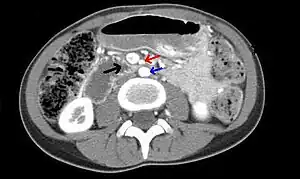

![]() | |

| Abdominal and pelvic computed tomography scan showing duodenal compression (black arrow) by the superior mesenteric artery (red arrow) and the abdominal aorta (blue arrow). | |

Diagnosis is can be difficult, and usually one of exclusion. SMA syndrome is generally considered only after people have undergone an extensive evaluation of their gastrointestinal tract including upper endoscopy, and evaluation for various malabsorptive, ulcerative and inflammatory instestinal conditions with a higher diagnostic frequency. Diagnosis may follow X-ray examination revealing duodenal dilation followed by abrupt constriction proximal to the overlying SMA, as well as a delay in transit of four to six hours through the gastroduodenal region. Standard diagnostic exams include abdominal and pelvic computed tomography (CT) scan with oral and IV contrast, upper gastrointestinal series (UGI), and, for equivocal cases, hypotonic duodenography. In addition, vascular imaging studies such as ultrasound and contrast angiography may be used to indicate increased bloodflow velocity through the SMA or a narrowed SMA angle.[13][14]

It is typically caused by an angle of 6°–25° between the AA and the SMA, in comparison to the normal range of 38°–56°, due to a lack of retroperitoneal and visceral fat (mesenteric fat). In addition, the aortomesenteric distance is 2–8 millimeters, as opposed to the typical 10–20.[15] However, a narrow SMA angle alone is not enough to make a diagnosis, because people can have a narrow SMA angle with no symptoms of SMA syndrome.[16]